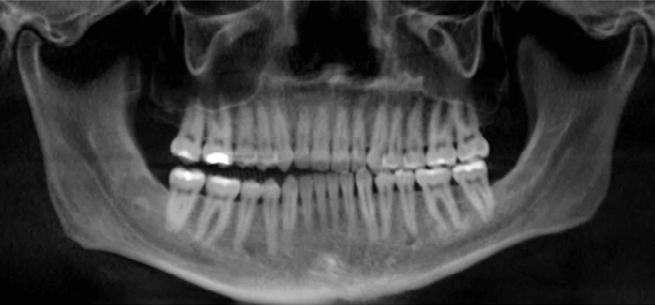

Clinical evaluation showed a mild Class III skeletal pattern with a constricted maxilla, mildly dolichofacial and straight

profile (Figure 1). Full adult dentition was present with all third molars extracted. Maxillary and mandibular incisors were normoclined. The maxillary midline coincided with the facial midline, and the mandibular midline was 2 mm to the right of the facial midline. There was a 2 mm to 5 mm lateral open bite on the right side from the second molar to the lateral incisor, and the maxillary occlusal plane was canted to the left of the interpupillary line. A lateral tongue thrust into the open bite was noted on swallow.

The right side was in posterior crossbite and there was an edge-to-edge anterior bite with wear on the maxillary central incisors. Mild gingival recession was noted, but soft tissue was generally within normal limits. CBCT analysis found no radiographic evidence of osteoarthritis in the TMJ joints, nor osseous or apical pathology involving the maxillary or mandibular teeth. His airway was not constricted. Initial report from the myofunctional therapist indicated that the patient never developed a mature swallow sequence and had a bilateral posterior tongue thrust.

Figure 1. Initial records.